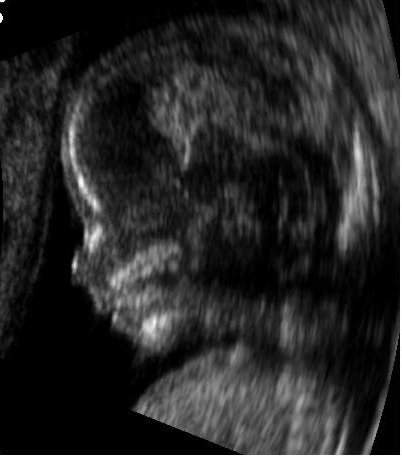

7. 2. 1. 진단 영상

'''의료 초음파'''는 근육, 힘줄, 그리고 많은 내부 장기들, 이들의 크기, 구조와 병리학적 손상을 실시간 단층 영상으로 가시화한, 초음파에 기반한 진단 의학촬영(medical image) 기술이다. 이는 주기적 또는 응급 상황에서 태아를 가시화하는 데도 사용된다. 초음파를 이용한 진단은 소노그라퍼(sonographer)라고 불리는 의료 전문가에 의해 수행된다. 산과용 초음파는 일반적으로 임신기간 동안에만 사용된다. 초음파는 적어도 50년 동안 인간의 몸속을 영상화하는 데 사용되었으며 현대 의학에서 가장 널리 사용되는 진단 기술 중 하나이며 상대적으로 저렴하고 이동이 용이하다.

초음파는 근육, 힘줄, 그리고 여러 내부 장기를 시각화하여 크기, 구조, 그리고 병변(lesion)을 실시간 단층 촬영 영상으로 포착하는 데 사용되는 초음파 기반 진단 의료 영상 기법이다. 초음파는 방사선과 전문의와 초음파 전문가에 의해 최소 50년 동안 인체 영상화에 사용되어 왔으며 널리 사용되는 진단 도구가 되었다.[35] 이 기술은 자기공명영상(MRI)이나 컴퓨터 단층촬영(CT)과 같은 다른 기법에 비해 비교적 저렴하고 휴대가 간편하다. 초음파는 또한 정기 및 응급 산전 진료 중 태아를 시각화하는 데에도 사용된다. 임신 중 사용되는 이러한 진단 응용 프로그램은 산과 초음파 검사라고 한다. 현재 의료 분야에 적용되는 바와 같이, 적절하게 수행된 초음파는 환자에게 알려진 위험이 없다.[36] 초음파 검사는 이온화 방사선을 사용하지 않으며, 영상화에 사용되는 전력 수준은 조직에 역효과를 일으키는 가열이나 압력 효과를 발생시키기에 너무 낮다.[37][38]